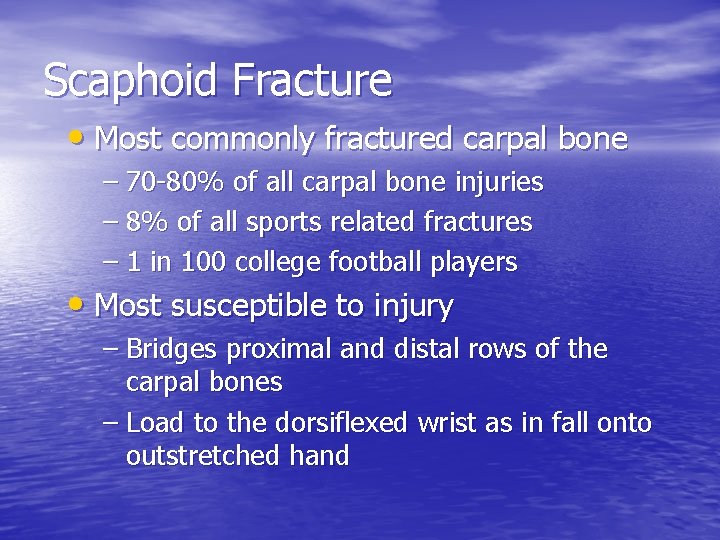

Scaphoid Fracture • Most commonly fractured carpal bone – 70 -80% of all carpal bone injuries – 8% of all sports related fractures – 1 in 100 college football players • Most susceptible to injury – Bridges proximal and distal rows of the carpal bones – Load to the dorsiflexed wrist as in fall onto outstretched hand

Scaphoid Fracture • Painful, swollen wrist after a fall • Tenderness in snuffbox • High frequency of nonunion and avascular necrosis • Initial x-rays often unremarkable